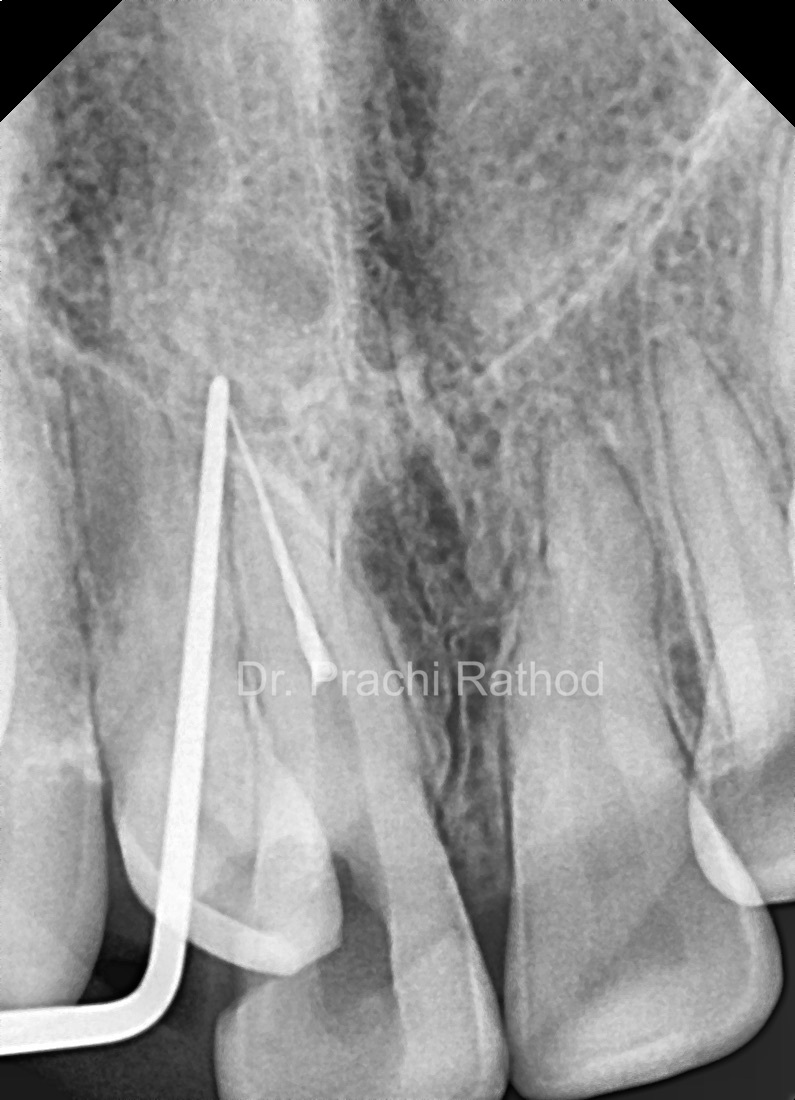

Pre Op RVG

Visible Broken File